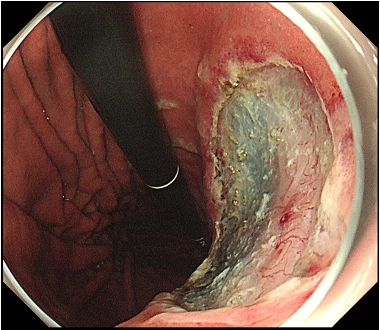

図4: 切除後の創部をクリップで閉鎖(サンプル)

図4. 切除後の創部は、出血の予防策として内視鏡的にクリップで閉鎖します。